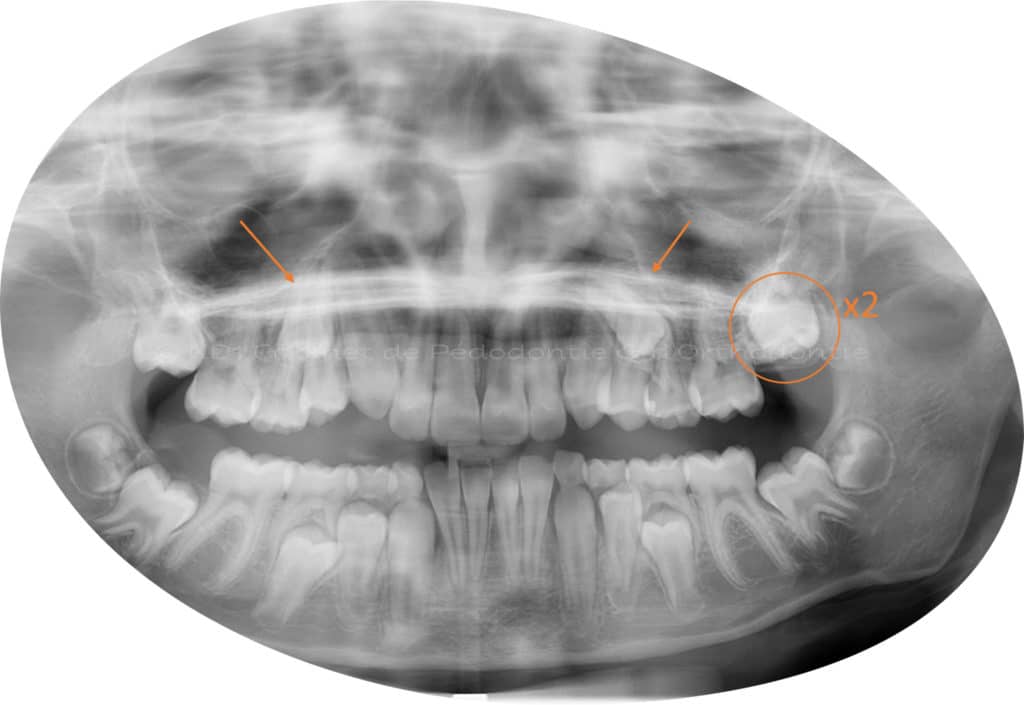

Cas #1 – Traitement avec des bagues, deuxièmes prémolaires et dent de sagesse supérieures ectopiques.